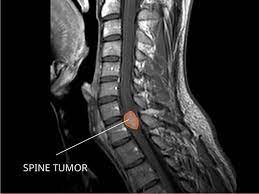

Spinal Cancer And Spinal Tumors Johns Hopkins Medicine

Spinal Cancer And Spinal Tumors Johns Hopkins Medicine from www.hopkinsmedicine.org

Spinal tumor and spinal cancer diagnosis when a tumor is found anywhere in the spine, the first step is usually to determine whether it is a primary or a metastatic tumor.